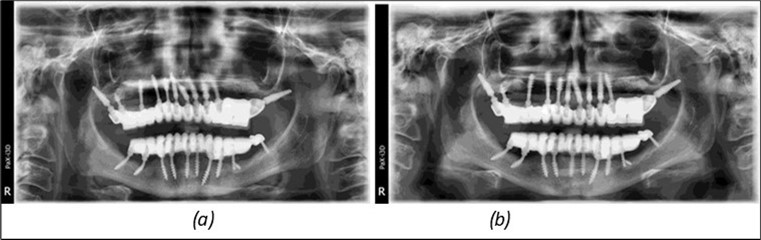

Figure 3.Panoramic pictures after removal of implants affected by peri-implantitis, extractions, alveolar crest regularization, and insertion of corticobasal and TPG implants (07.2022)

Panoramic pictures after removal of implants affected by peri-implantitis, extractions, alveolar crest regularization, and insertion of corticobasal and TPG implants (07.2022)

Figure 14.Rx panoramic final situation control: (a) Panoramic X-ray with the addition of a distal BCS implant in quadrant 3 at 11.2022; (b) Control X-ray, 10.2023.

Rx panoramic final situation control: (a) Panoramic X-ray with the addition of a distal BCS implant in quadrant 3 at 11.2022; (b) Control X-ray, 10.2023.

Figure 15.Follow-up panoramic X-ray 09.2025

Follow-up panoramic X-ray 09.2025

The results of rehabilitation treatment with corticobasal and compressive implants with a polished surface after the failure of two stage implants were highlighted over a period of 3 years and 3 months as being very good (Figure 14, Figure 15), with the patient completing a satisfaction survey in this regard. Certainly, it is necessary to continuemonitoring these results in the long term.